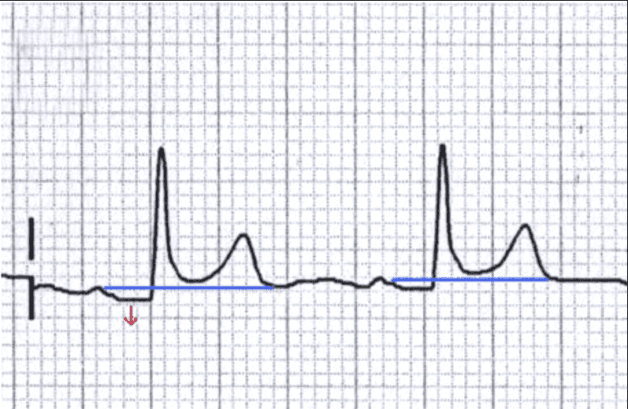

Điện tâm đồ (viết tắt ECG) là một đường cong ghi lại các biến thiên của dòng điện do tim phát ra khi hoạt động co bóp. ECG có thể đo tốc độ, nhịp điệu của tim cũng như cung cấp các bằng chứng về lưu lượng máu đến tim một cách gián tiếp.

Thiếu máu cơ tim sẽ cho thấy hình ảnh sóng T trên điện tâm đồ dẹt, âm.

Vị trí phát ra nhịp bất thường như nút xoang, nút nhĩ thất, cơ tim và bất thường dẫn truyền một chiều của tim sẽ cho ra hình ảnh nhịp tim bất thường thông qua xét nghiệm ECG.